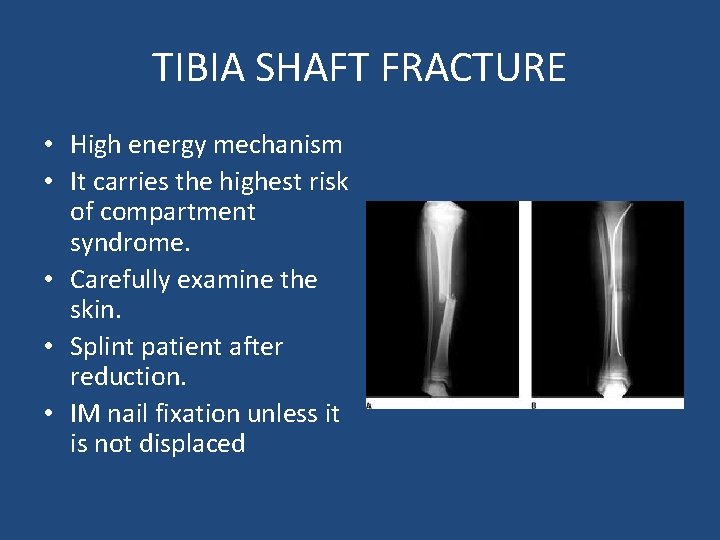

TIBIA SHAFT FRACTURE • High energy mechanism • It carries the highest risk of compartment syndrome. • Carefully examine the skin. • Splint patient after reduction. • IM nail fixation unless it is not displaced